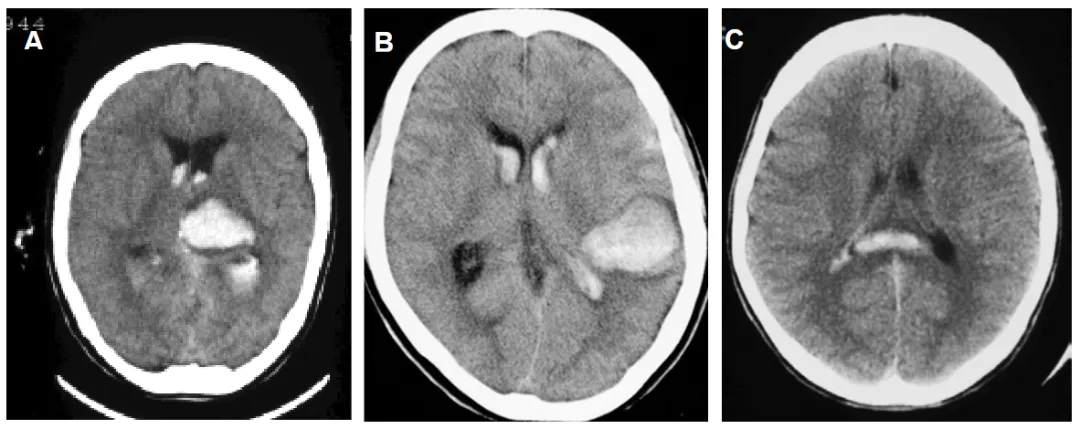

后部出血的代表性 CT 图像

A:丘脑出血 | B:颞叶后半部出血 | C:胼胝体后半部出血